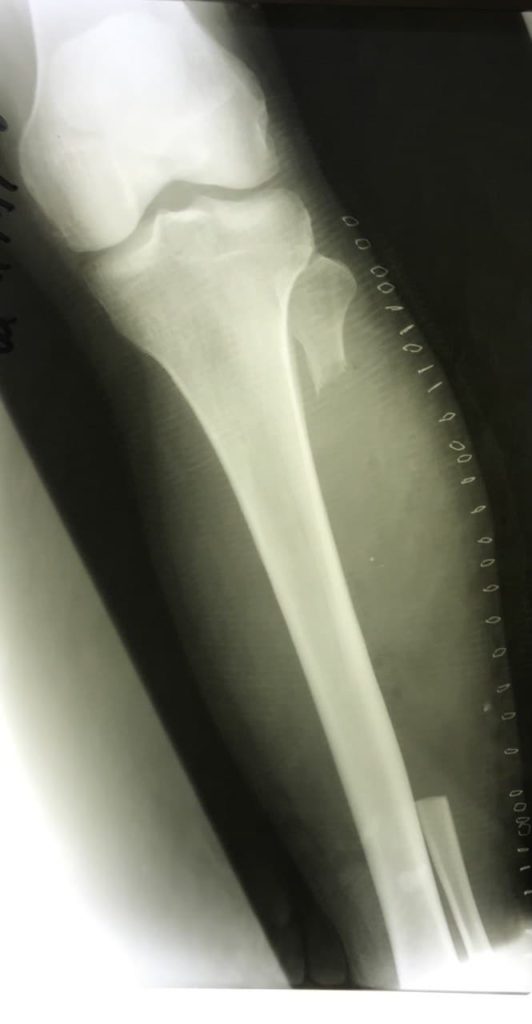

Встановлено діагноз: Ліпосаркома – злоякісна пухлина м’яких тканин.

Через 3 міс. діагностовано рецидив пухлини та проведено дистанційну променеву терапію в сумарній опромінюваній дозі 50 Грей.

Враховуючи характер захворювання, проростання в кістку та малогомілковий нерв.

15.09.2020р. проведено хірургічне втручання: Висічення рецидиву пухлини м’яких тканин лівої гомілки з резекцією лівої малогомілкової кістки та малогомілкового нерва. Операція тривала 2,5 год та пройшла з мінімальною втратою крові.